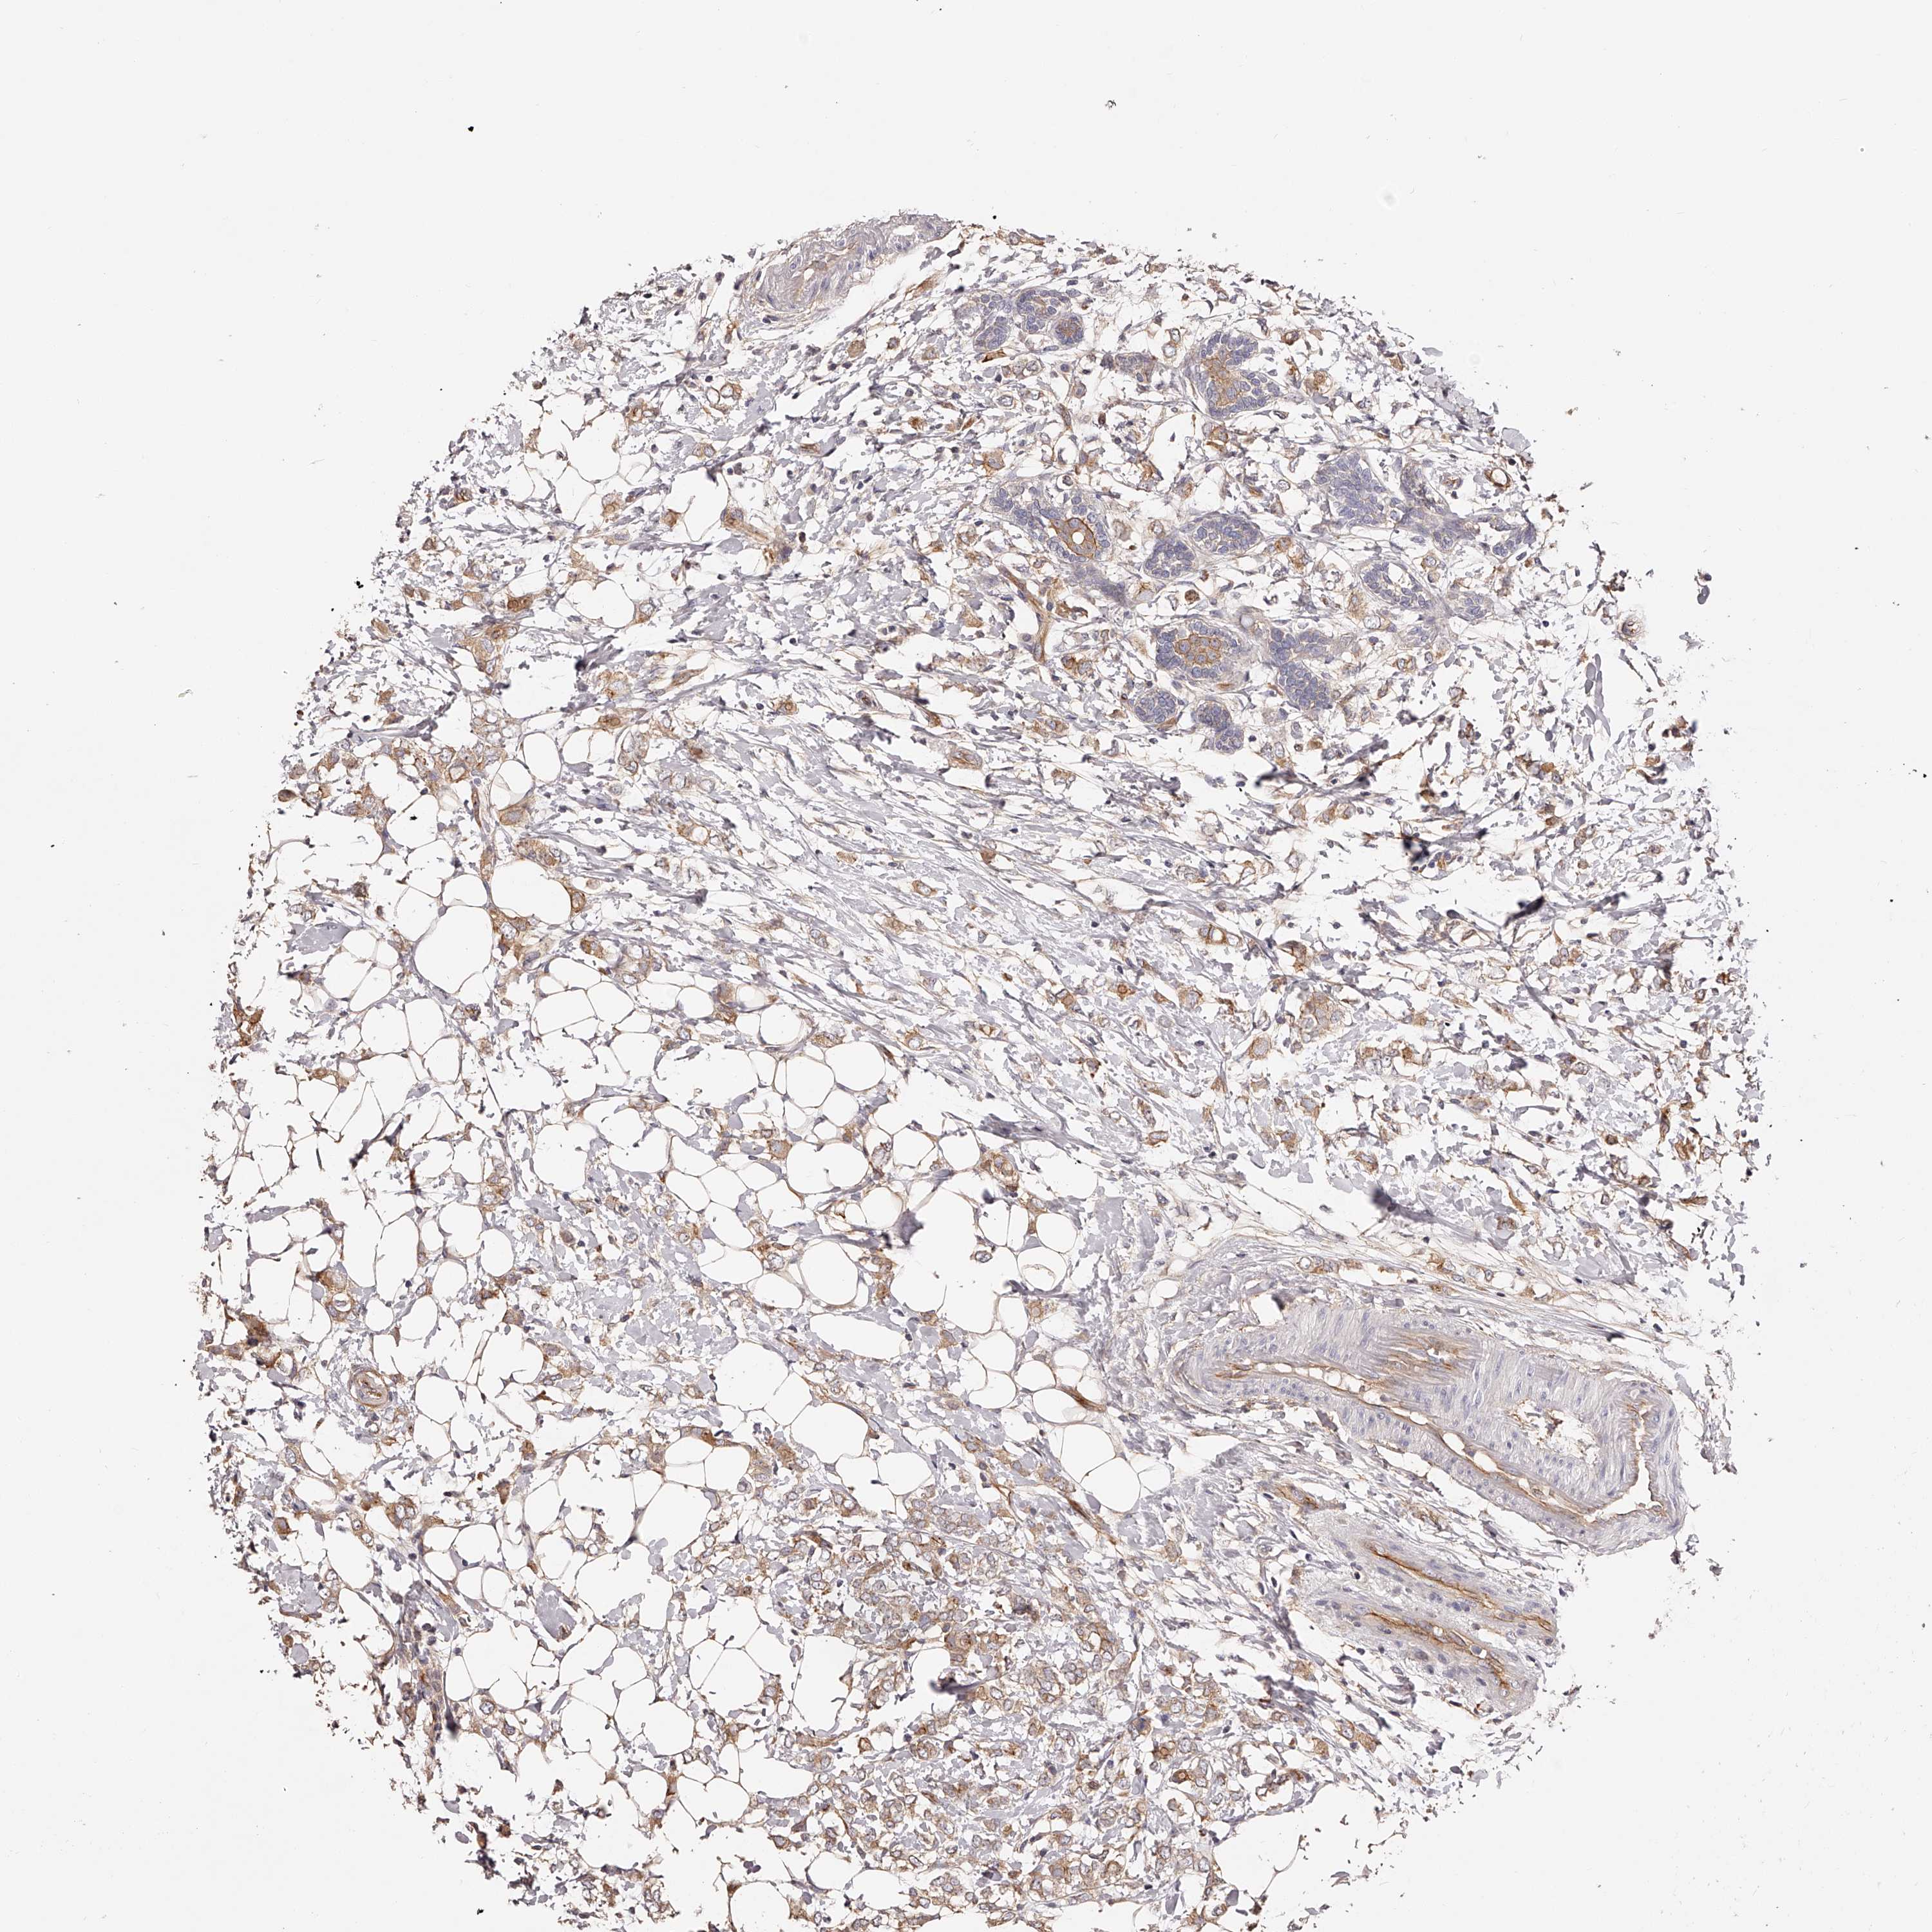

BRCA TCGA BRCA VALIDATION PROTEIN EXPRESSION